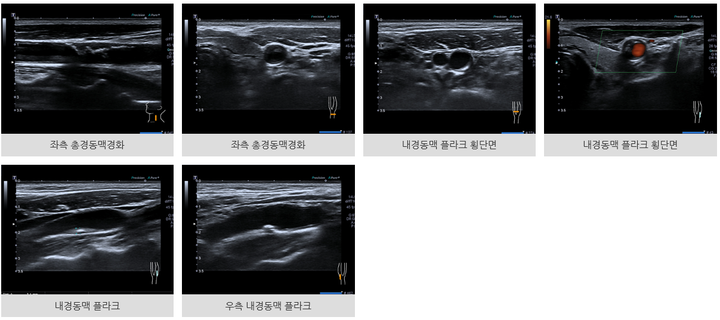

경동맥 초음파 검사는 고주파 음파를 이용하여 경동맥의 상태를 확인하는 비침습적인 검사입니다. 검사과정은 다음과 같습니다.

- 초음파 발사: 초음파 탐촉자를 목 부위에 대고 초음파를 발사합니다.

- 내부 영상화: 발사된 초음파가 경동맥 내부를 반사하면서 영상으로 나타냅니다.

- 경동맥 상태 확인: 경동맥의 혈관벽, 혈류 속도, 혈류 방향, 혈전 등을 확인합니다.